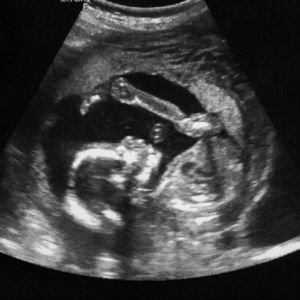

2D Ultrasound Imaging

2D ultrasound is used for basic imaging of internal organs, such as the liver, kidneys, and heart, providing clear and essential diagnostic information.